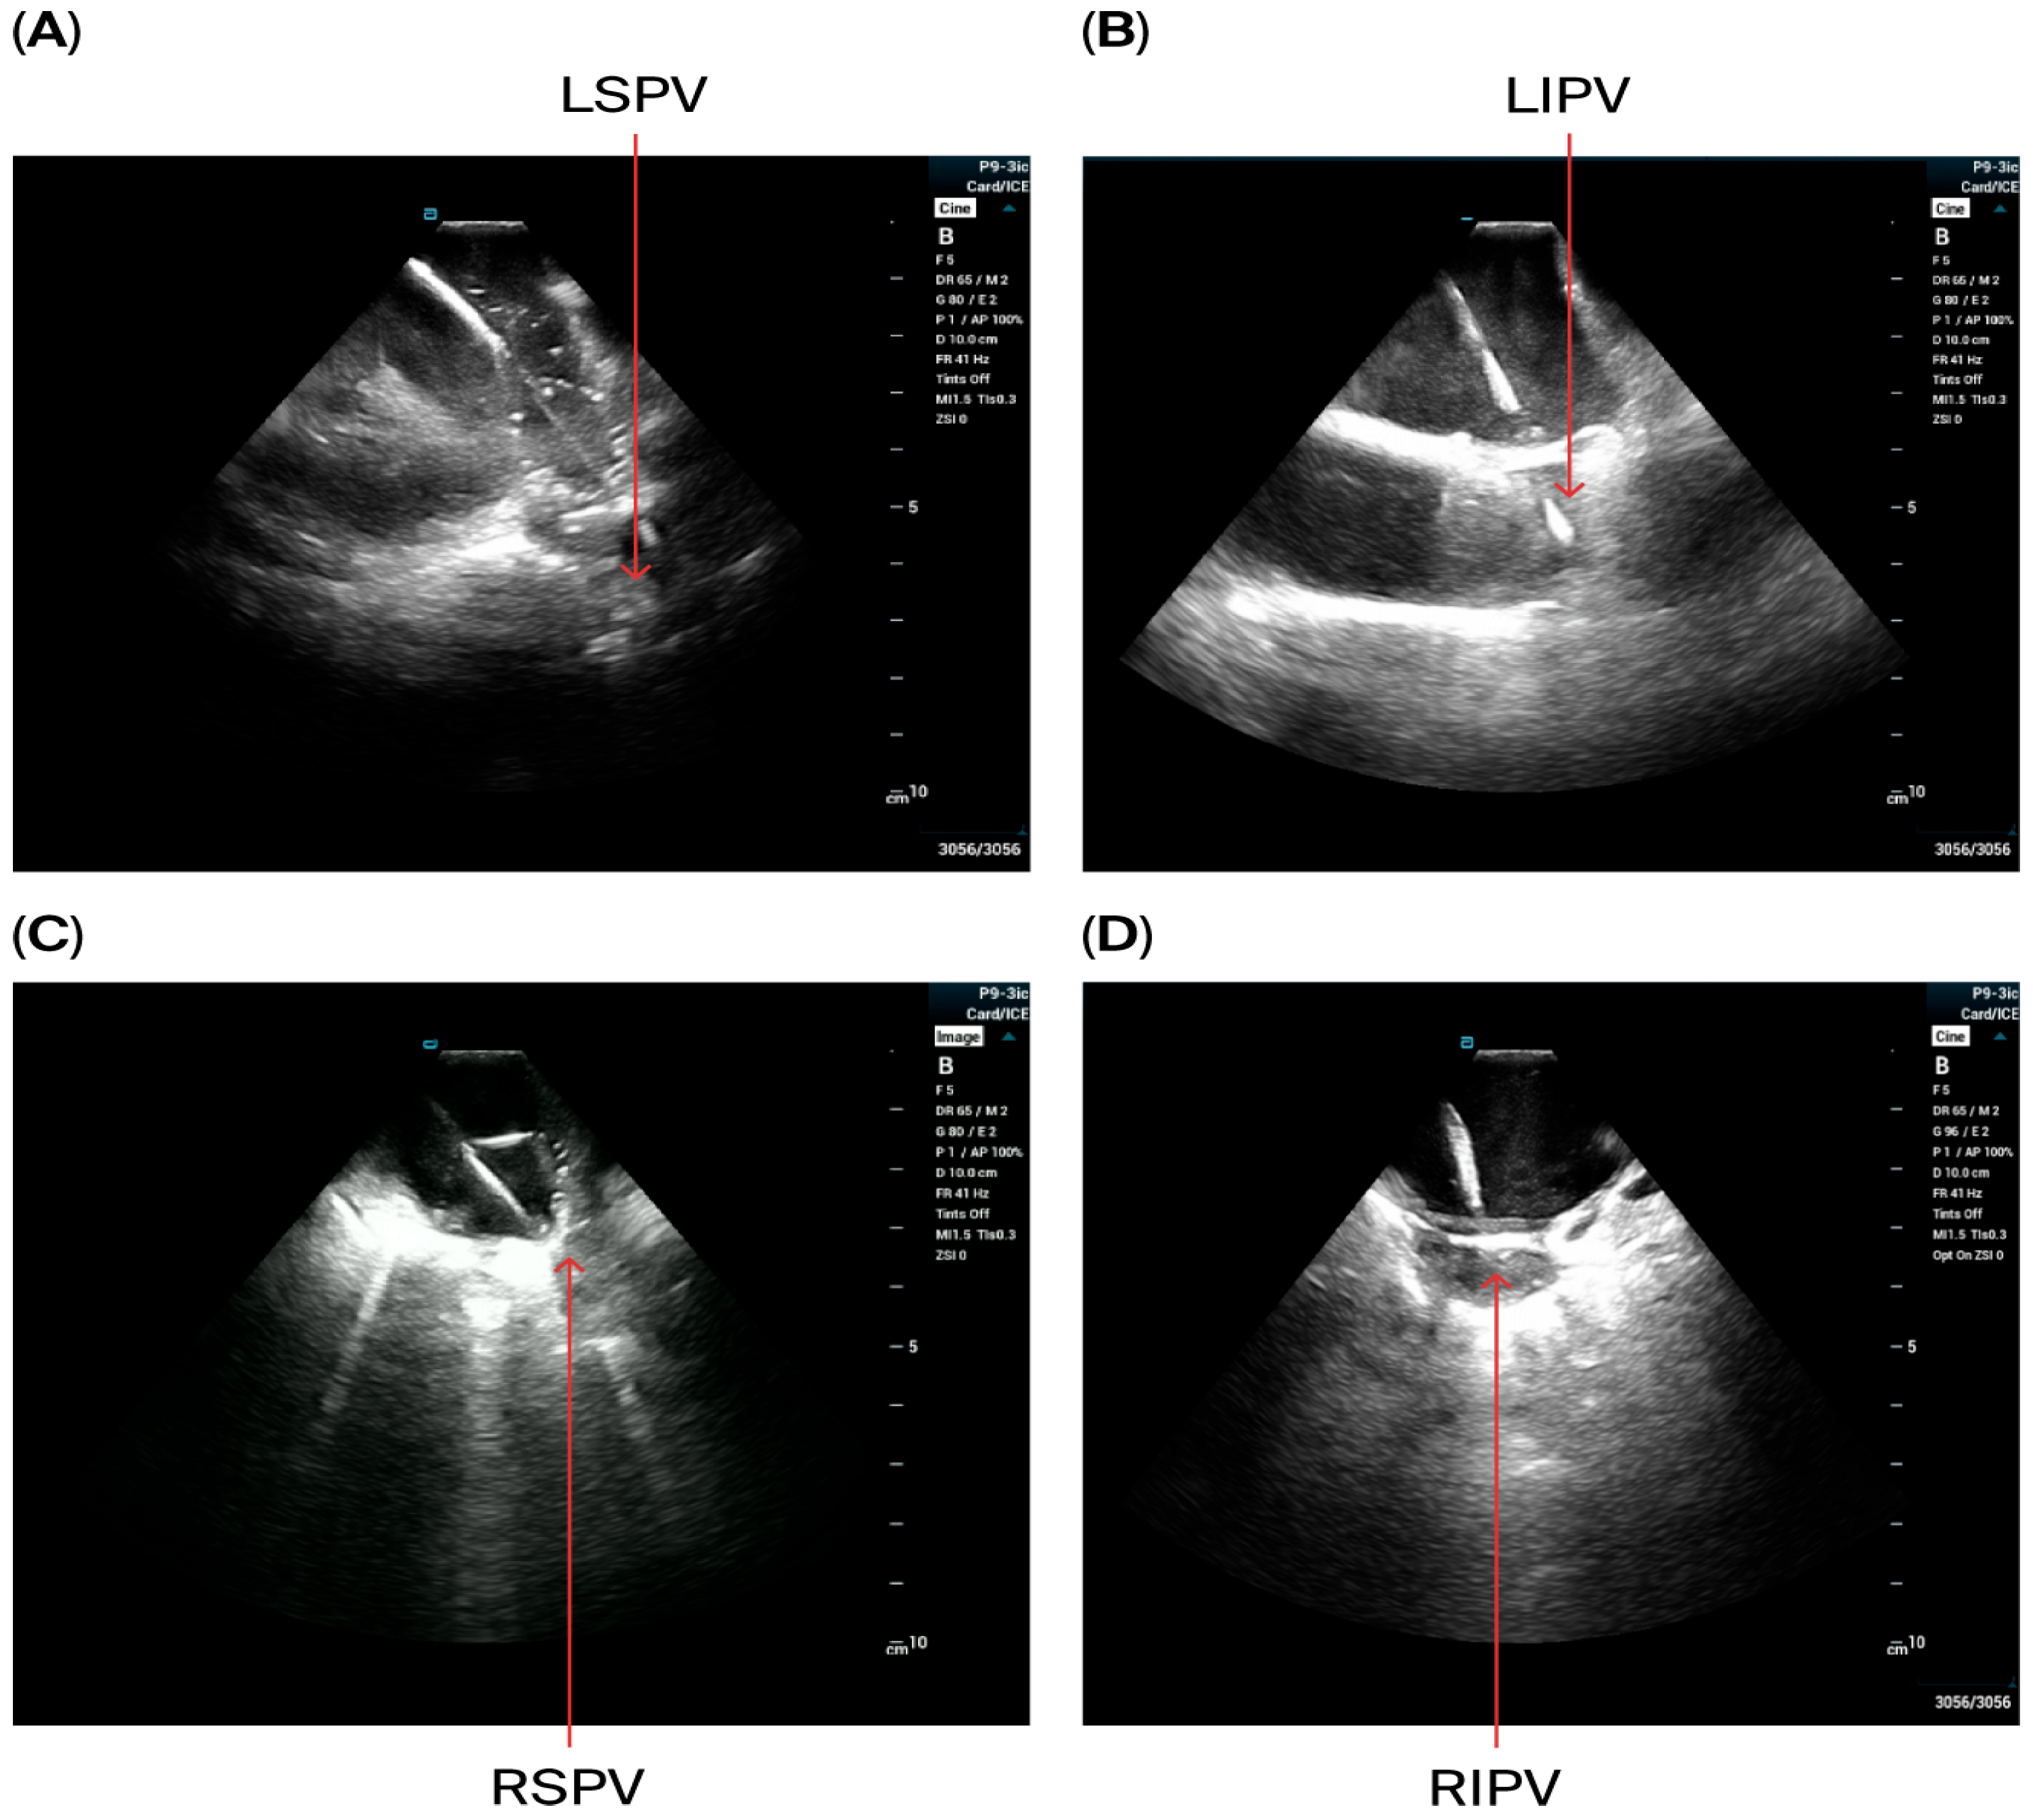

- The VersaCross sheath was exchanged for the Faradrive sheath and dilatator. After predilatation of transseptal puncture, the Faradrive sheath was retracted, and the ICE catheter was advanced along the VersaCross wire to the left atrium (Figure 1A–D). Then, the Faradrive sheath was moved back to the LA, and the dilator and Versacross wire were removed, with the ICE catheter and PFA sheath placed in the LA via a single transseptal puncture.

- ICE images of the LA, including the LAA, were obtained from all patients to exclude LAA thrombus (Figure 1E).

- A circular mapping catheter (CMC) or high-density catheter (with repeated ablation) was advanced to the LA via the Faradrive sheath. Electroanatomic mapping of the LA, including detailed voltage assessment was performed. Then, over the J-tip wire, the Farawave pentaspline catheter was advanced to the LA via the Faradrive sheath. The 0.035-inch J-tip guidewire was attached to the EnSite mapping system’s pin box via a DuoMode extension cable (Boston Scientific, Marlborough, MA, USA) for additional visualization in LA and pulmonary veins. ICE catheter imaging was used to ensure appropriate catheter positioning and catheter–tissue contact with each PV and LAPW PFA lesion delivered. Prior to ablation, 0.2 mg of intravenous glycopyrrolate was administered to all patients to avoid vagal reactions during PVI.

- PV isolation was performed with the PFA catheter placed at the PV ostium, with 4 applications in the basket configuration and 4 in the flower configuration for a total of 8 applications per PV. Appropriate rotation of the catheter following 2 applications in each position was assured with LA ICE and EAM visualization. Two additional applications in the flower configuration were delivered at the operator’s discretion in the left and right carina, towards the LA ridge and septal aspect of the right pulmonary veins based on the anatomy and presence of atrial potentials.